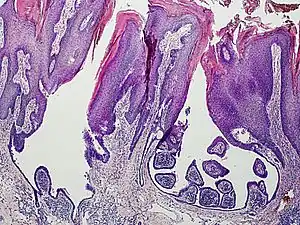

a) Syringocystadenoma papilliferum over a pre-existing nevus-sebaceous b) histopathology of syringocystadenoma papilliferum showing cystic invagination of surface epithelium -

An example of a syringocystadenoma papilliferum